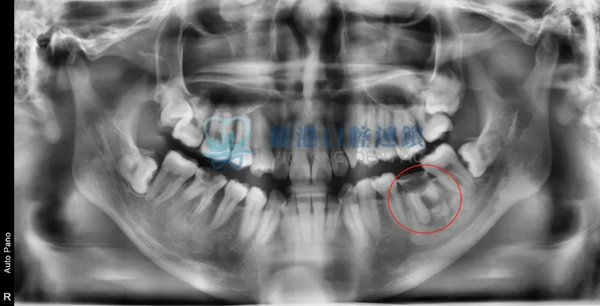

輕微案例